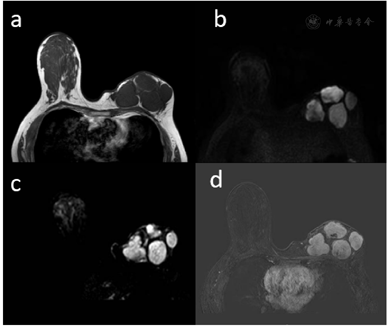

行乳腺MRI增强所见:左乳形态失常,内见四枚肿块,较大者约34 mm×27 mm,边缘清楚,T1WI信号减低,DWI信号值增高,增强后明显强化,强化欠均匀。

左乳MRI增强提示:左乳多发肿块,建议手术活检(BI-RADS 4类)(图4)。